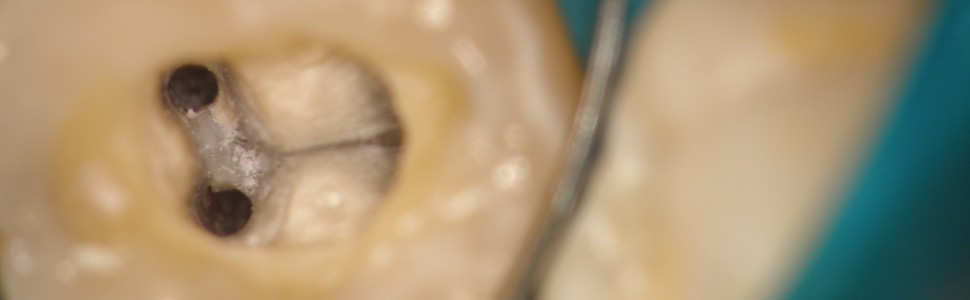

Mężczyzna w wieku 27 lat został poddany leczeniu endodontycznemu, którego konieczność wynikała z jatrogennej perforacji korzeni zębów 36 i 37 wywołujących stan zapalny miazgi i przyzębia. Perforacje powstały podczas próby wprowadzenia mikroimplantów ortodontycznych niezbędnych do leczenia ortodontycznego stanowiącego etap leczenia przedprotetycznego. Po diagnostyce opartej m. in. o obrazowanie CBCT, perforacje w obu zębach zamknięto z użyciem mikroskopu zabiegowego materiałami biozgodnymi i przeprowadzono leczenie endodontyczne. Nie usuwano tkwiących w kości i w tkankach zęba złamanych wierteł przygotowujących przestrzeń pod planowane mikroimplanty ortodontyczne. Czteroletni okres obserwacji pozwolił potwierdzić słuszność podjętej decyzji o pozostawieniu zarówno zębów, jak i nie usuwaniu złamanych fragmentów wierteł.

A 27-year-old male underwent endodontic treatment, the necessity of which was due to the iatrogenic perforation of the roots of teeth 36 and 37, causing pulpitis and periodontitis. Perforations formed during an attempt to introduce orthodontic microimplants necessary for orthodontic treatment constituting a stage of pre-prosthetic treatment. After diagnostics based on e.g. o CBCT imaging, perforations in both teeth were filled with a surgical microscope with biocompatible materials and endodontic treatments were performed. Broken drills stuck in the bone and in the tissues of the teeth, which prepared the space for the planned orthodontic microimplants, were not removed. The four-year observation period allowed to confirm the correctness of the decision made to keep both the teeth and not to remove the broken drill parts.